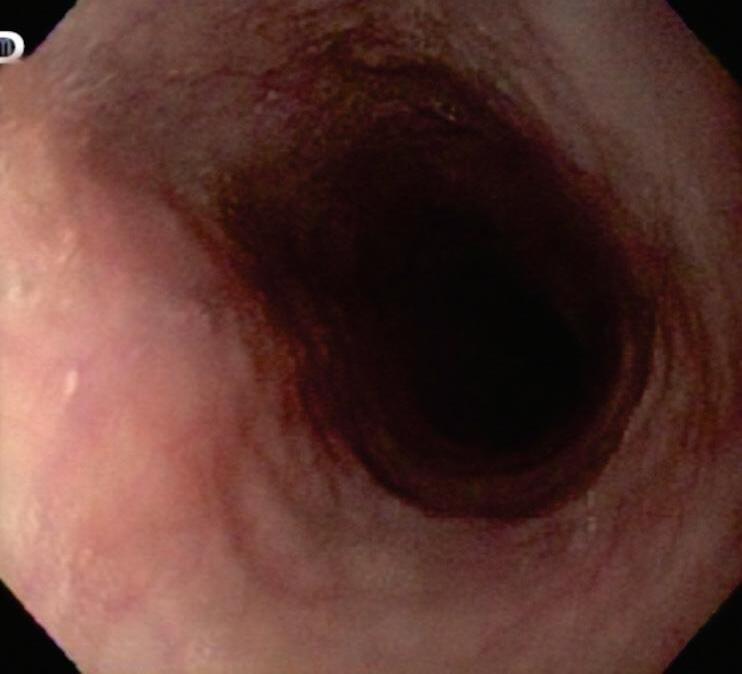

DIAGNÓSTICO

Uma distinção deve ser feita entre o manejo dos sintomas da dispepsia não investigados e o diagnóstico de DF. A definição de Roma IV de DF implica que os potenciais distúrbios orgânicos subjacentes já tenham sido descartados pela endoscopia ou por outras avaliações complementares. Nos pacientes que apresentam sintomas dispépticos, as diretrizes recomendam a endoscopia digestiva alta (EDA) àqueles com idade acima de 40 a 50 anos para descartar neoplasia e fazer biópsias a fim de estabelecer o status do H. pylori. A EDA também é obrigatória em pacientes mais jovens que apresentam sinais de alarme, embora estes tenham um valor limitado na predição de uma doença orgânica. Em indivíduos mais jovens sem sintomas de alarme, as diretrizes concordam que não há necessidade de realizar EDA para detectar malignidade, o que é raro. A terapia empírica, seja com inibidores da bomba de prótons (IBP), procinéticos ou para a erradicação do H. pylori (“estratégia de testar e tratar”), é valiosa para o manejo da dispepsia não investigada. Ao considerar o diagnóstico de certeza de DF, a EDA mostra-se fundamental para descartar não apenas malignidades, mas também doenças orgânicas benignas que podem explicar os sintomas, como úlcera péptica (prevalência de 8%), esofagite (20%) ou gastrite associada ao H. pylori. Na decisão por fazer ou não o exame endoscópico, convém levar em consideração a epidemiologia local de câncer gástrico.5-9